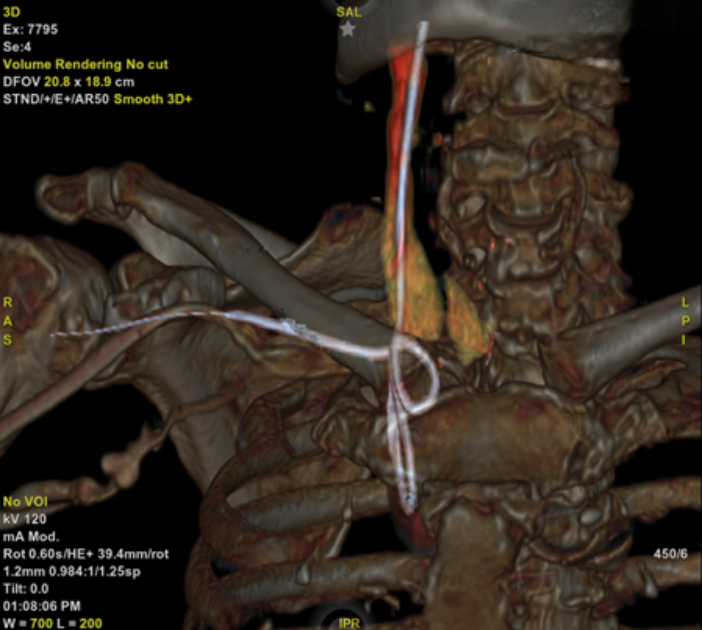

We present the case of a 79-year-old woman admitted to another hospital unit for dyspnoea at rest, fever and hypotension. The final diagnosis was community-acquired pneumonia and septic shock. Initiation of amines and placement of a right subclavian central venous catheter were required. During the procedure, resistance to the advancement of the guidewire was detected, which could not be extracted. The control X-ray revealed knotting that prevented the removal of the guidewire (figure 1), necessitating referral to the interventional cardiology service of our centre for percutaneous extraction. Prior to the decision to extract, a computed tomography (CT) with three-dimensional reconstruction was performed, which demonstrated the intravascular position of the guidewire (figure 2).

A right femoral venipuncture was performed using an 8 French introducer, and fluoroscopy was employed to visualise the distal end of the knotted guide. The EN Snare 12–20 mm three-loop snare wire extraction device (Merit Medical, Salt Lake City, US) was utilised to snare the tip of the wire under fluoroscopic guidance and extract it completely via the right femoral route. It was removed without complications (figure 3).